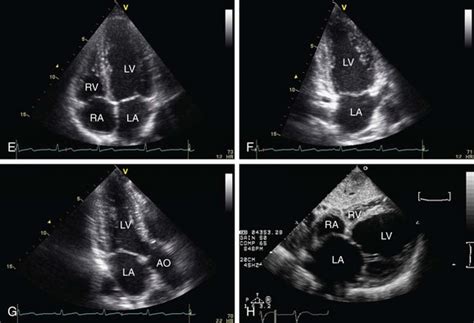

Alright, let’s explore the standard echocardiography views that form the backbone of cardiac imaging. These views provide comprehensive information about the heart’s anatomy and function. Each view is carefully selected to visualize specific structures and detect particular abnormalities. We’ll cover the parasternal, apical, subcostal, and suprasternal notch views, detailing their importance and the key anatomical landmarks they reveal.

The parasternal views are acquired by placing the transducer along the left sternal border. These views are fundamental for assessing the left ventricle, right ventricle, and aortic valve. There are two primary parasternal views: the long-axis and short-axis views. The parasternal long-axis view (PLAX) provides a longitudinal image of the heart, visualizing the left ventricle, right ventricle, left atrium, mitral valve, aortic valve, and ascending aorta. This view is particularly useful for measuring the left ventricular dimensions, assessing mitral valve function, and evaluating aortic valve stenosis or regurgitation. Common pathologies identified in the PLAX view include left ventricular hypertrophy, aortic stenosis, mitral valve prolapse, and pericardial effusion. The parasternal short-axis view (PSAX) is obtained by rotating the transducer 90 degrees from the PLAX position. This view provides a cross-sectional image of the heart, allowing visualization of the left ventricle at different levels, including the mitral valve, papillary muscles, and apex. The PSAX view is essential for assessing regional wall motion abnormalities, which can indicate myocardial ischemia or infarction. It is also used to evaluate the right ventricle, pulmonary artery, and tricuspid valve. Common pathologies identified in the PSAX view include regional wall motion abnormalities, right ventricular enlargement, and pulmonary hypertension. Mastering these parasternal views is crucial for any echocardiographer, as they provide a wealth of information about the heart’s structure and function. So, practice those transducer movements and get comfortable with identifying the key anatomical landmarks!

Apical Views

The apical views are obtained by placing the transducer at the apex of the heart, typically in the fifth intercostal space along the midclavicular line. These views are excellent for assessing the left ventricular apex, mitral valve, and left atrium. The apical four-chamber view provides a comprehensive image of all four chambers of the heart, allowing for evaluation of chamber size, wall thickness, and valve function. This view is particularly useful for assessing mitral and tricuspid regurgitation, as well as detecting atrial and ventricular septal defects. Common pathologies identified in the apical four-chamber view include dilated cardiomyopathy, hypertrophic cardiomyopathy, atrial fibrillation, and congenital heart defects. The apical two-chamber view is obtained by rotating the transducer from the apical four-chamber view, aligning it with the left ventricle and left atrium. This view is ideal for assessing left ventricular regional wall motion and evaluating mitral valve stenosis or regurgitation. The apical long-axis view, also known as the apical three-chamber view, is obtained by further rotating the transducer from the apical two-chamber view, bringing the aorta into view. This view provides a longitudinal image of the left ventricle, left atrium, and aorta, allowing for assessment of aortic valve function and detection of aortic aneurysms or dissections. The apical views are essential for a complete echocardiographic examination, providing valuable information about left ventricular function and valvular abnormalities. So, make sure you’re comfortable with these views and their anatomical landmarks!

Subcostal Views

The subcostal views are obtained by placing the transducer below the ribcage, typically in the epigastric region. These views are particularly useful when the parasternal and apical views are difficult to obtain due to body habitus or lung disease. The subcostal four-chamber view provides a similar image to the apical four-chamber view, allowing for evaluation of all four chambers of the heart. This view is especially helpful for assessing atrial and ventricular septal defects, as well as detecting pericardial effusions. The subcostal short-axis view provides a cross-sectional image of the left ventricle, similar to the parasternal short-axis view. This view is useful for assessing regional wall motion abnormalities and evaluating the right ventricle. The subcostal views are valuable tools for obtaining echocardiographic images in challenging patients, ensuring that a comprehensive cardiac assessment can be performed regardless of body size or lung condition. So, keep these views in your toolkit for those tough cases!